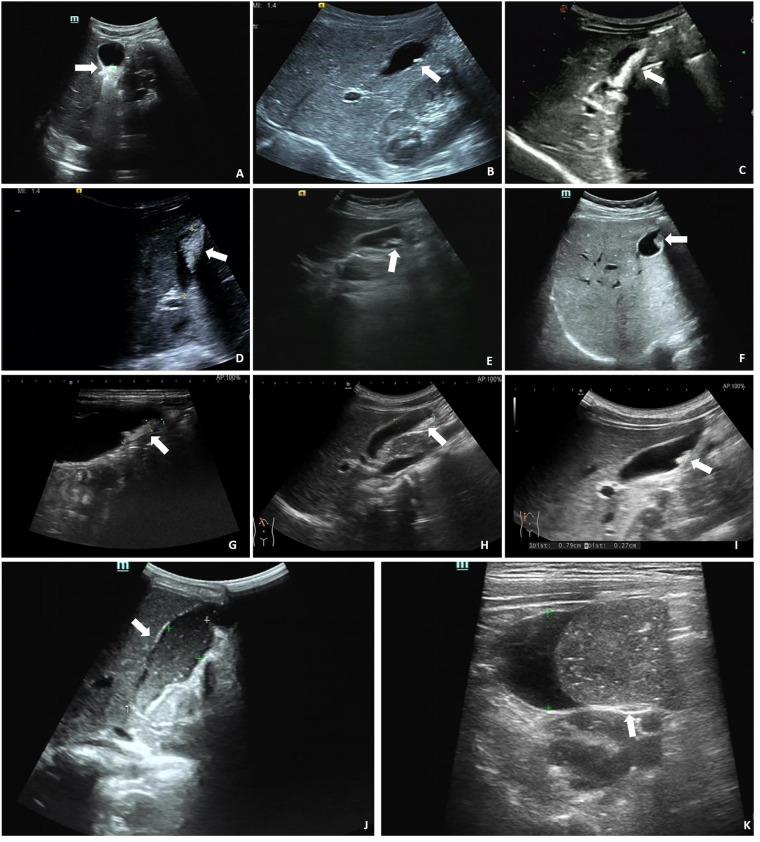

PL was diagnosed in 18.4% of patients treated with CTX, primarily through ultrasound, which revealed hyperechoic material within the gallbladder. Compared with the non-PL group, patients with PL were older and taller, with no significant differences in CTX dosage ( = 0.915). Patients with PL also had higher rates of digestive and neurological infections (both  < 0.001). Serum analysis revealed distinct liver and kidney function markers in the PL group, including lower levels of total bile acids, adenosine deaminase, and lactate dehydrogenase, and higher creatinine levels (all  < 0.05). Discontinuation of CTX led to symptom resolution in most cases, and all cases of PL resolved within three months.

The occurrence of PL is not significantly related to CTX dosage. Furthermore, the rate of CTX metabolism and excretion may play a key role in PL development. Overall, the findings demonstrate that ultrasound is an effective tool for monitoring the development of PL in children receiving CTX and that discontinuation of CTX could be an effective treatment for PL.

接受CTX治疗的患者中,18.4%被诊断为PL,主要通过超声诊断,超声显示胆囊内有高回声物质。与非PL组相比,PL组患者年龄更大、身高更高,CTX剂量无显著差异(P = 0.915)。PL组患者消化系统和神经系统感染率也更高(均P < 0.001)。血清分析显示PL组肝肾功能指标不同,包括总胆汁酸、腺苷脱氨酶和乳酸脱氢酶水平较低,肌酐水平较高(均P < 0.05)。在大多数情况下,停用CTX可使症状缓解,所有PL病例在三个月内均得到缓解。

PL的发生与CTX剂量无显著相关性。此外,CTX的代谢和排泄速率可能在PL的发生中起关键作用。总体而言,研究结果表明超声是监测接受CTX治疗儿童PL发展的有效工具,停用CTX可能是治疗PL的有效方法。